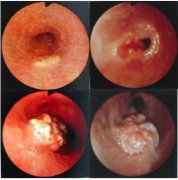

食管癌是常見的消化道腫瘤,全世界每年約有30萬人死于食管癌。其發(fā)病率和死亡率各國差異很大。我國是世界上食管癌高發(fā)地區(qū)之一,每年平均病死約15萬人。男多于女,發(fā)病年齡多在40歲以上...

食管癌發(fā)生于世界各國,其高發(fā)區(qū)有顯著的地理性差異。2000多年以前中國豫西一帶已有噎膈的記載。多數(shù)學(xué)者認(rèn)為食管癌是由環(huán)境中的致癌因素引起。已提出的致癌因素包括亞硝胺類化合物和...